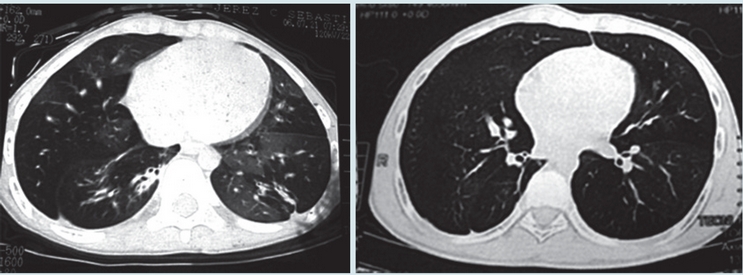

En las Figuras 1 y 2 se observan imágenes diagnósticas de algunos de nuestros pacientes y en la Figura 3 la evolución favorable de la tomografía (en un caso) después de varios años de seguimiento. En nueve casos se realizó exploración funcional respiratoria encontrando obstrucción significativa de la vía aérea en seis, obstrucción leve en dos y ausencia de obstrucción en uno; en 3/8 pacientes se observó reversibilidad del volumen espiratorio forzado en el primer segundo (VEF1). Se hizo seguimiento de la función pulmonar en cuatro pacientes observándose deterioro de la misma en tres (Figura 4). En cuanto a la presión pulmonar se encontró inicialmente elevada en el 43% de los casos, observándose en su seguimiento, disminución en cinco y aumento en uno.

En los casos en que se hizo tomografía de control, con un rango de tiempo entre los dos estudios de 31 a 80 meses, observamos mejoría en las imágenes en 6/8 pacientes. No encontramos en la literatura datos sobre seguimiento de imágenes en bronquiolitis obliterante post-infecciosa que nos permitan hacer una comparación al respecto.